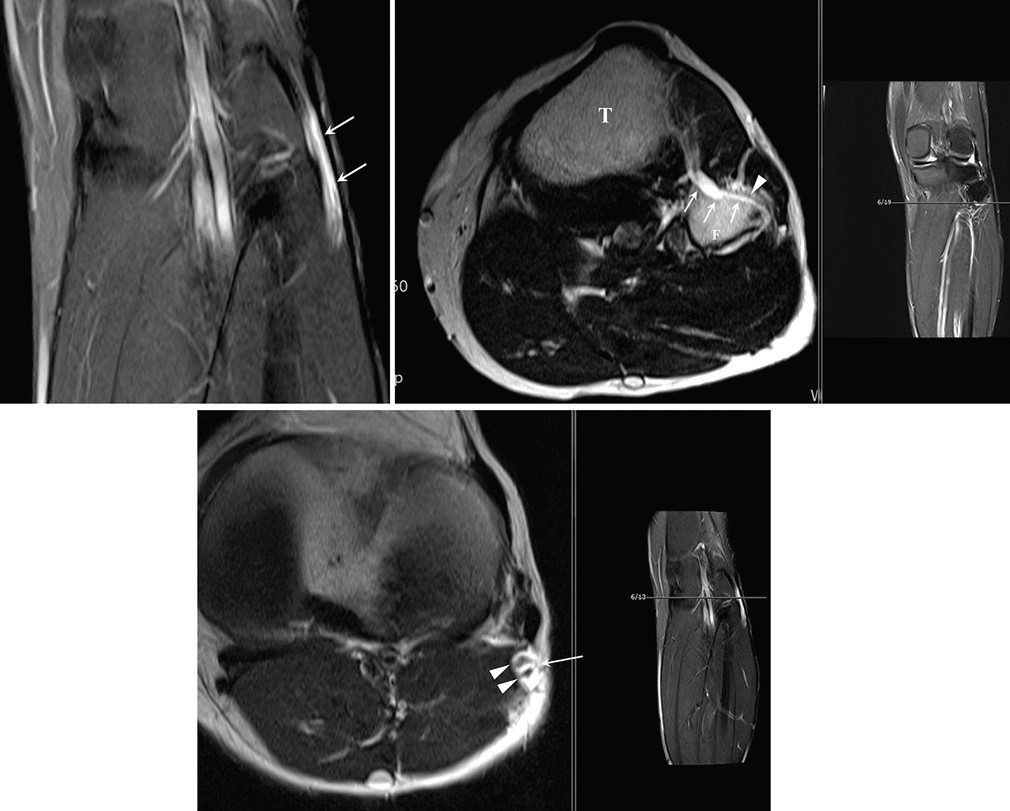

| 신경내 결절종 MRI 검사사진.[서울성모병원 제공] |

이러한 특성 때문에 일반적인 낭종 제거술로는 완치가 어려운 만큼, 관절과 연결된 신경 분지를 근본적으로 차단하는 정교한 수술 기법 적용이 필요할 수 있음을 제시했다.

특히 손 교수는 해당 연구를 통해 신경곁조직 아래막 결절종이 일반적인 결절종보다 신경 섬유에 더 밀착돼 있으며, 신경 줄기를 따라 매우 광범위하고 빠르게 전이될 수 있다는 사실을 확인했다.

이는 기존에 알려진 신경외막(epineurium) 내부의 결절종과는 달리, 신경을 감싸는 더 깊은 층인 신경곁조직 아래 공간을 따라 낭종이 확산되는 독특한 병태생리를 규명한 중요한 전환점이 됐다.